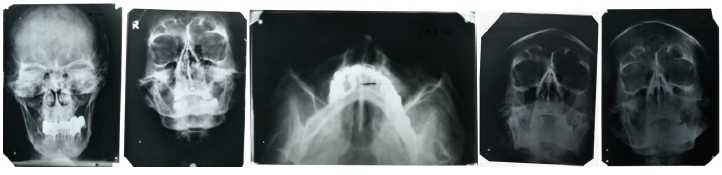

Второй образец, точнее, группа образцов из архива ФСБ (бывшего архива КГБ), представляет собой фрагмент верхней и три фрагмента нижней челюсти с зубами и коронками. Исследователи провели визуальное исследование костей и зубов под бинокуляром, элементный анализ костей и анализ поверхности зубов при помощи электронной микроскопии. Кроме того, в распоряжении экспертов оказались рентгеновские снимки головы, сделанные Гитлером в 1944 году, которые ранее хранились в США. Как видно на снимках, у него сохранилось только четыре целых собственных зуба (нижние резцы). Оказавшиеся у ученых фрагменты челюстей действительно содержали целые нижние резцы, а почти все остальные зубы были с металлическими коронками.

Рентгеновские снимки Адольфа Гитлера, сделанные в 1944 году